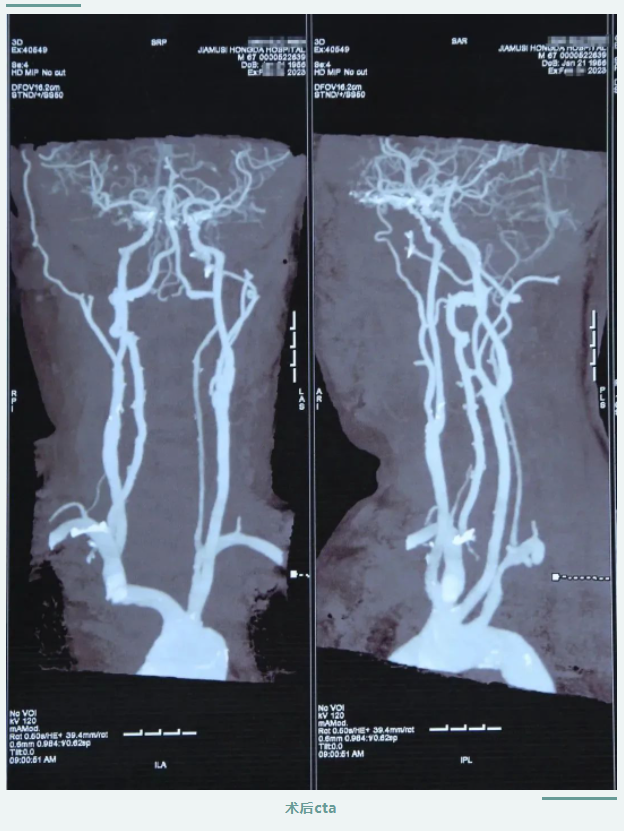

在醫(yī)護(hù)人員及患者家屬的精心照料下,患者術(shù)后狀態(tài)恢復(fù)良好,頭暈及肢體乏力明顯改善,肢體恢復(fù)知覺、可自主活動,言語清晰,感覺良好。